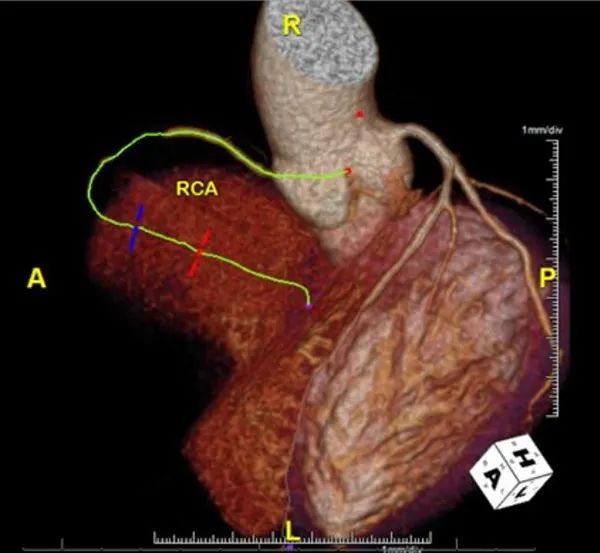

冠脉CTA显示非钙化性斑块,右冠状动脉中段完全闭塞,左前降支近段狭窄不到30%,左前降支中段狭窄低于50%(图1)。尽管冠脉CTA显示有冠心病,但其总冠脉钙化评分为0。

图1. 冠脉CTA影像。